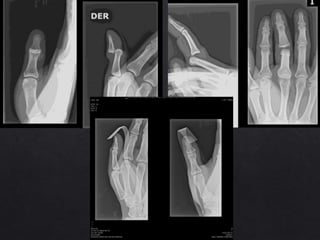

Luxación de Falanges

Clasificación de Eaton y Littler de Luxac. Dorsales:

• I Hiperextensión

• II Luxación dorsal

• II Luxación y fractura

Luxación de Falanges Clasificaciónde Eaton y Littler de Luxac. Dorsales: • I Hiperextensión • II Luxación dorsal • II Luxación y fractura